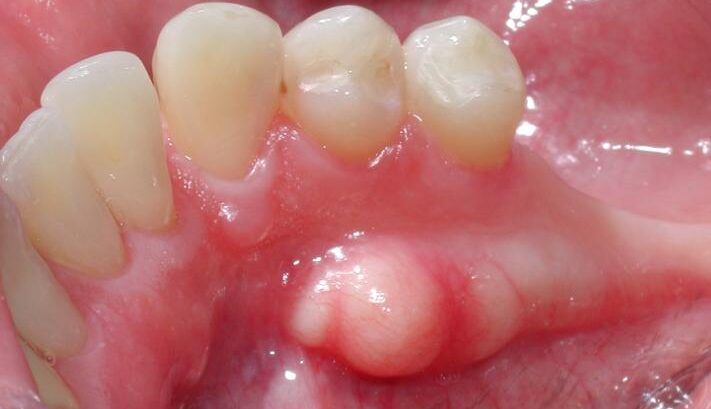

1. TORUS MANDIBULAR (Mandibular Tori)

Ubicación:

- Cara interna de la mandíbula (lado de la lengua)

- Zona de premolares (dientes 4 y 5)

- Por encima de la línea milohioidea (línea anatómica de la mandíbula)

- Generalmente BILATERAL (en ambos lados)

Aspecto:

- Bultos duros, lisos

- Pueden ser únicos o múltiples

- Tamaño variable (desde pequeños nódulos hasta masas grandes)

- Cubiertos por mucosa normal (rosada, lisa)

Prevalencia: 7-40% de la población (varía según etnia)